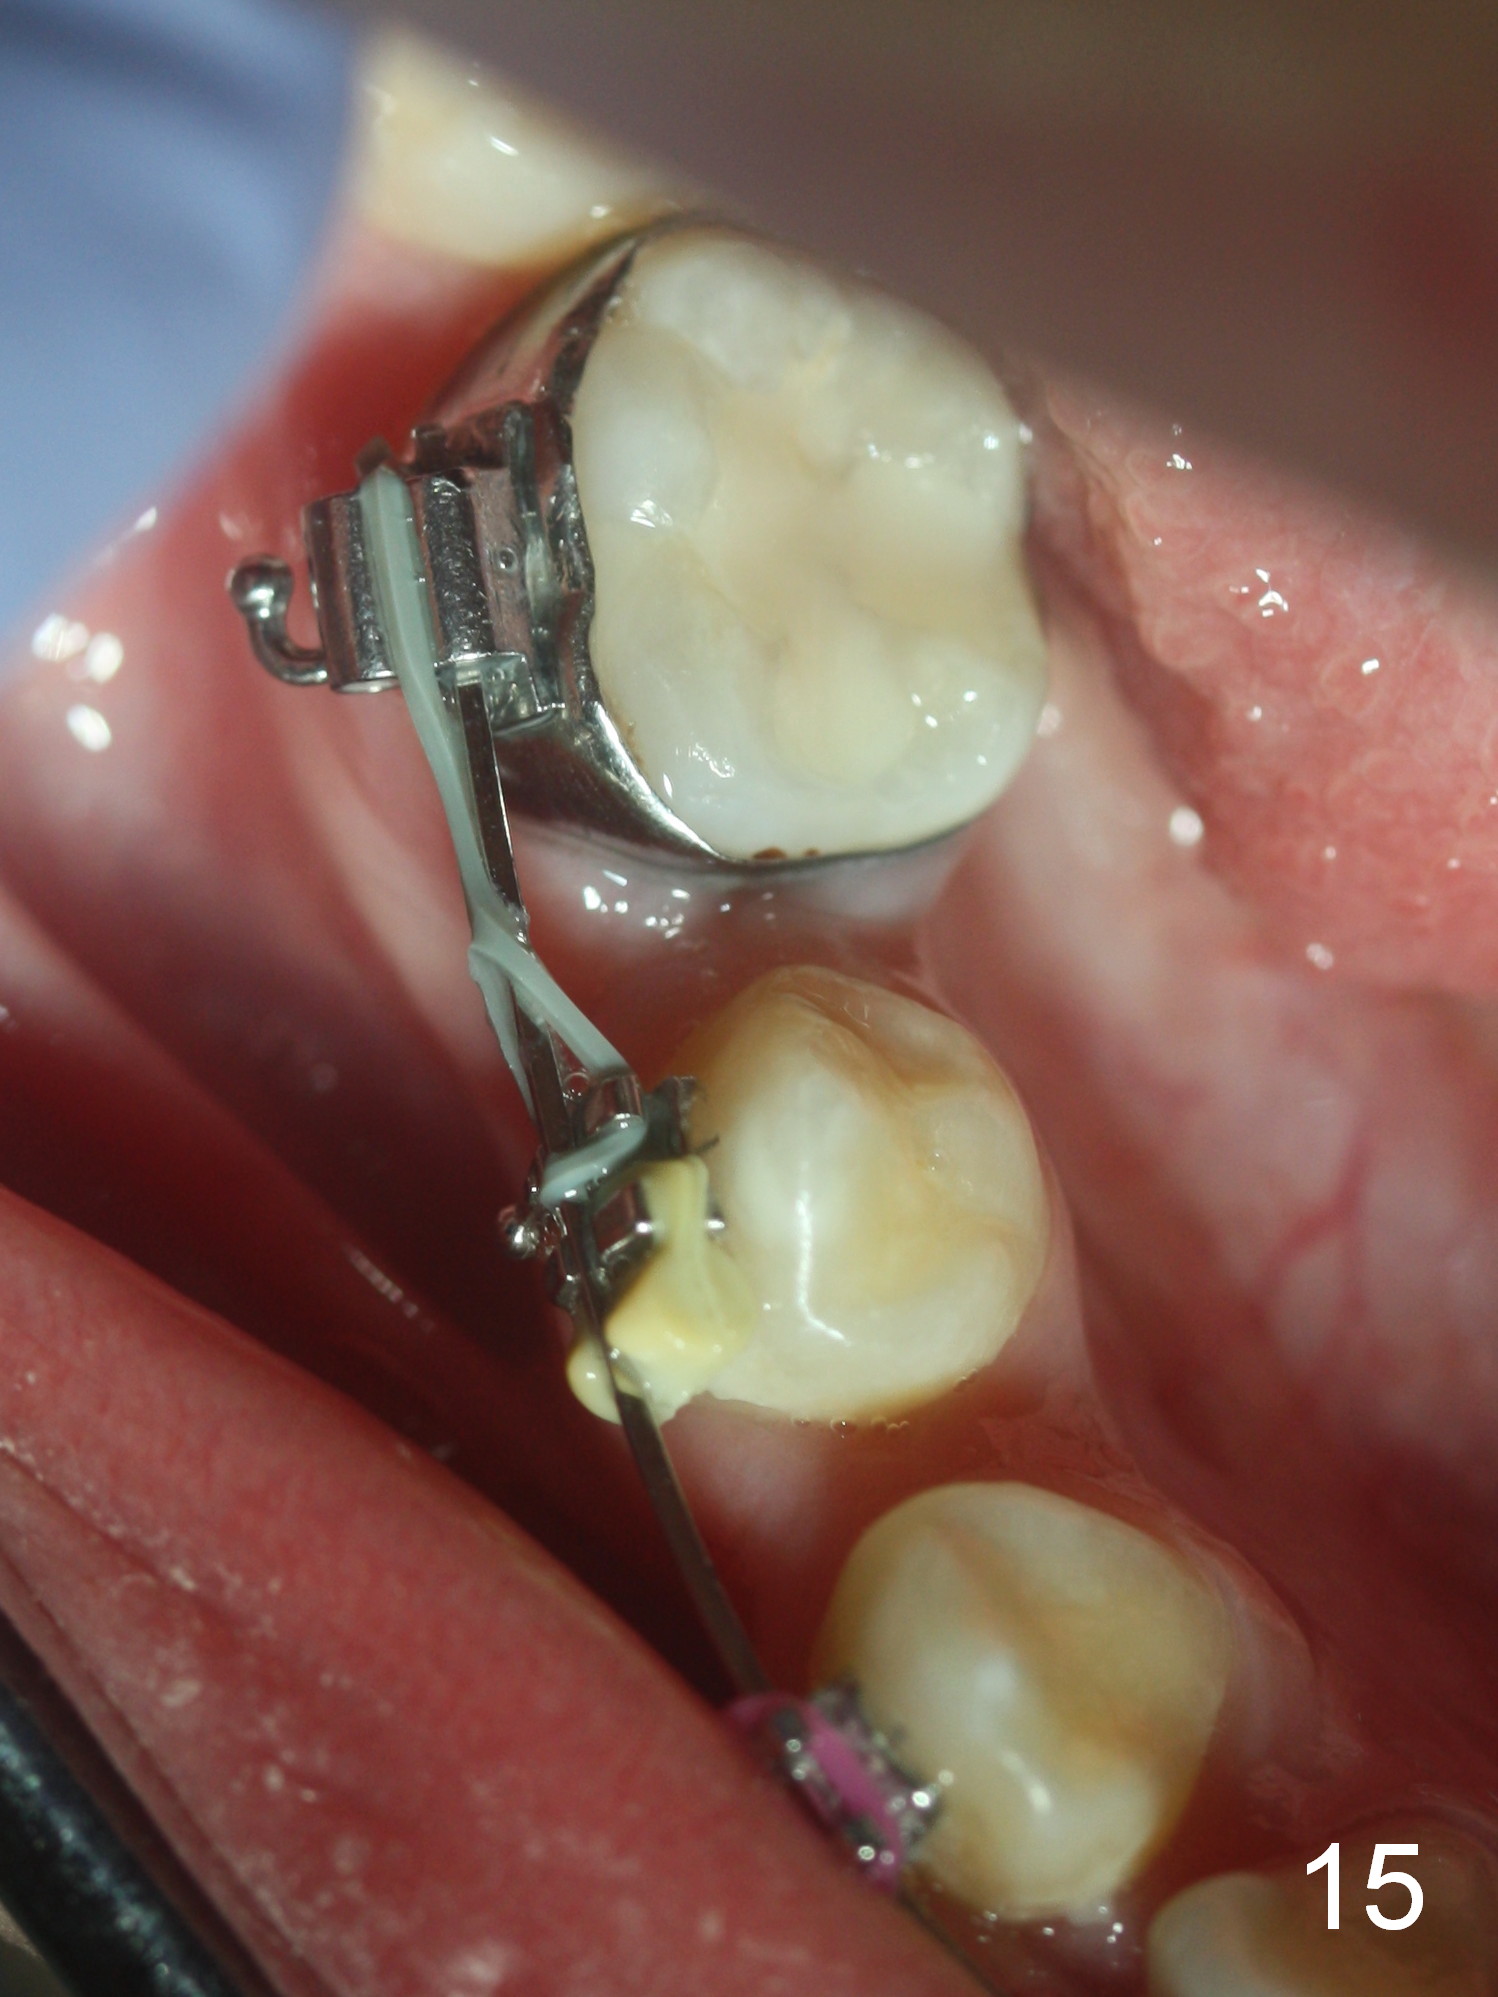

Approximately 4.5 months of power chains between 4s and 6s buccally, U4s contact U6s with rotation (Fig.13,14), while L4s have 1-2 mm to be distalized (Fig.15,16). With placement of lingual buttons on U4s and power chains lingually, the rotation should be corrected. The rotation wedges were placed with ligature wire on the left in the last visit. The patient returns 3 weeks later.